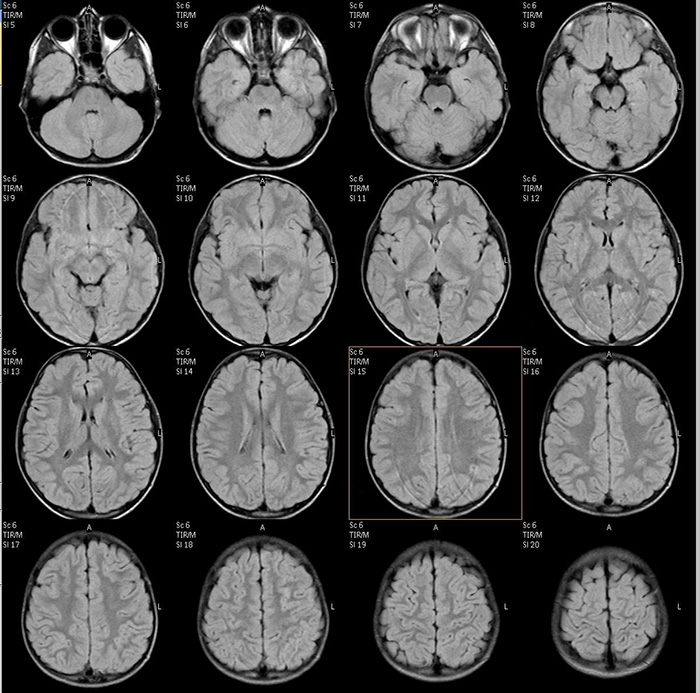

Рис 2.А.– автоматическая сегментация и рассчет объемов структур мозга по данным МРТ позволяет локализовать и оценить повреждения белого и серого вещества мозга.